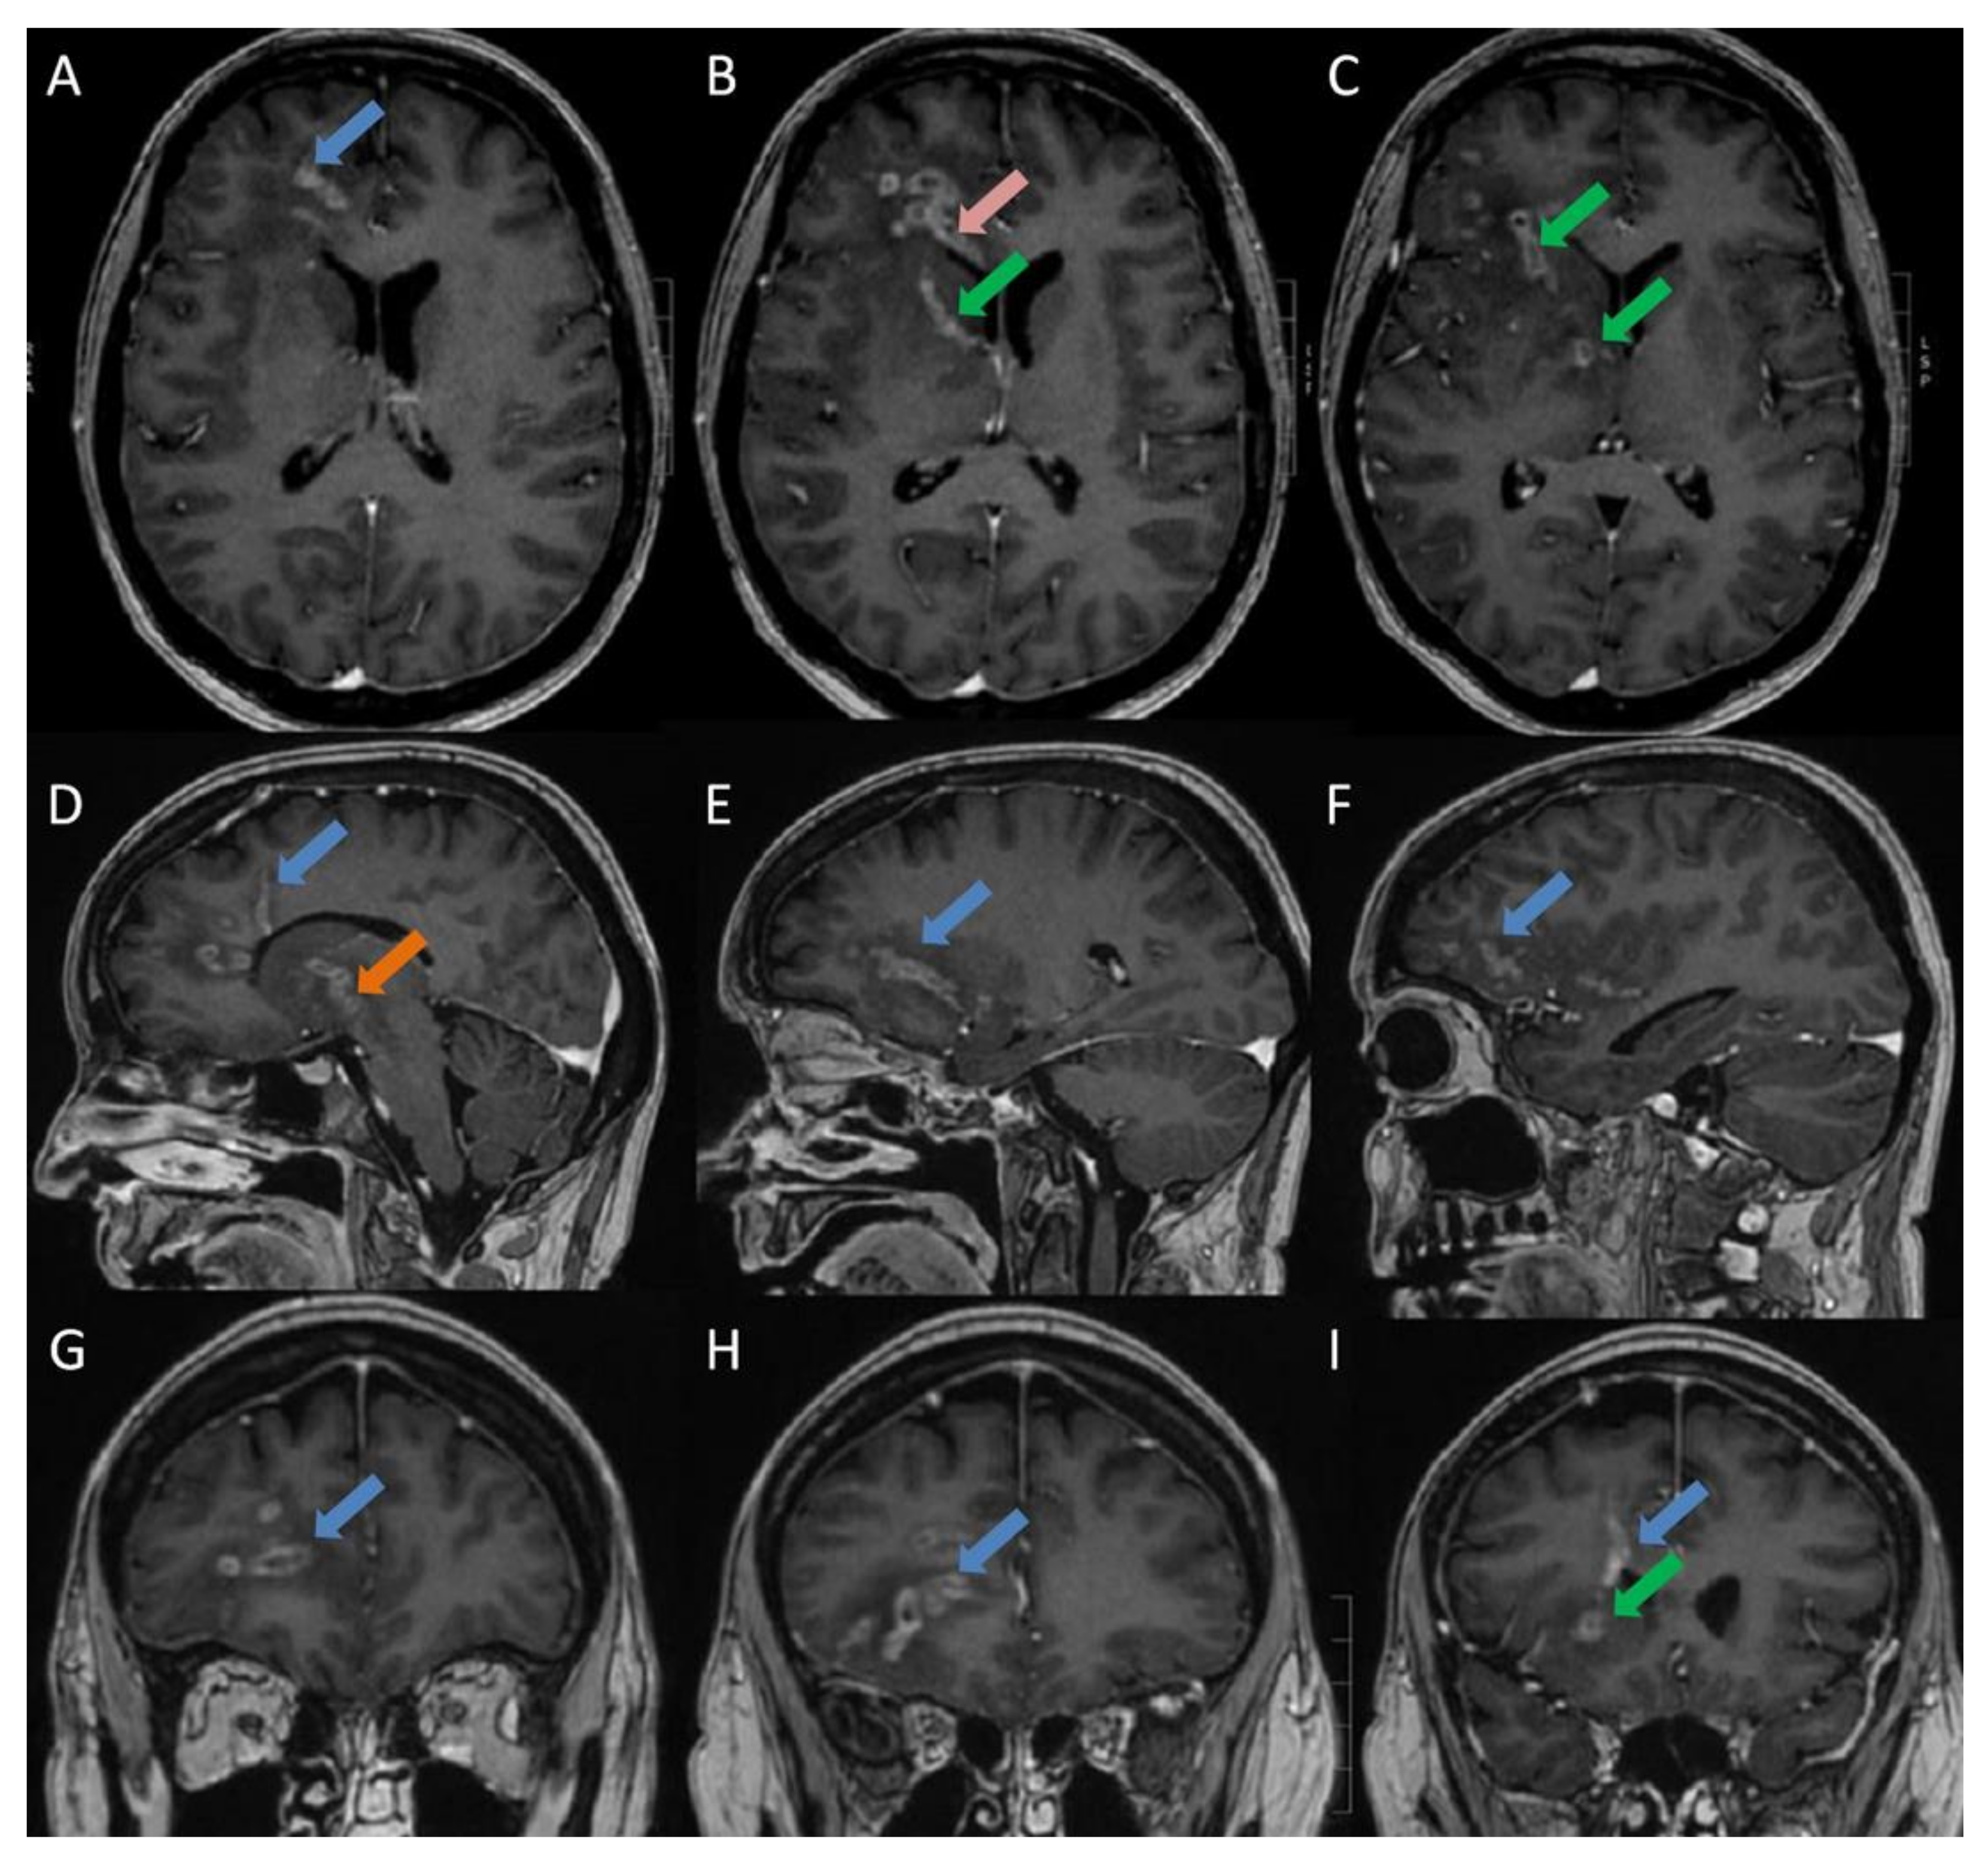

Listeria Monocytogenes Brain Abscesses in a Patient with Disseminated Non-Small Cellular Lung Cancer: MRI Findings

- Slezák, O.; Žižka, J.; Kvasnička, T.; Dvořáková, R.; Česák, T.; Ryšková, L.; Ryška, P.; Eliáš, P. Worm-like appearance of Listeria monocytogenes brain abscess: Pesentation of three cases. Neuroradiol. 2020, 62, 1189–1193. [Google Scholar] [CrossRef] [PubMed]